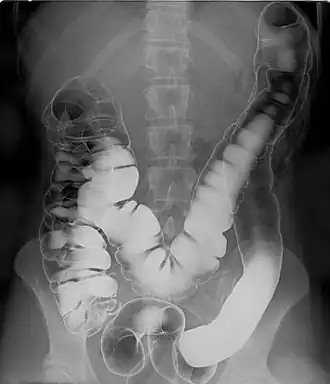

![]() Human intestinal tract, as imaged via double-contrast barium enema | |

A double-contrast barium enema is a form of contrast radiography in which x-rays of the colon and rectum are taken using two forms of contrast to make the structures easier to see.[1] A liquid containing barium (that is, a radiocontrast agent) is put into the rectum. Barium (usually as a sulfate) outlines the colon and rectum on an x-ray and helps show abnormalities. Air is also put into the rectum and colon to further enhance the x-ray.